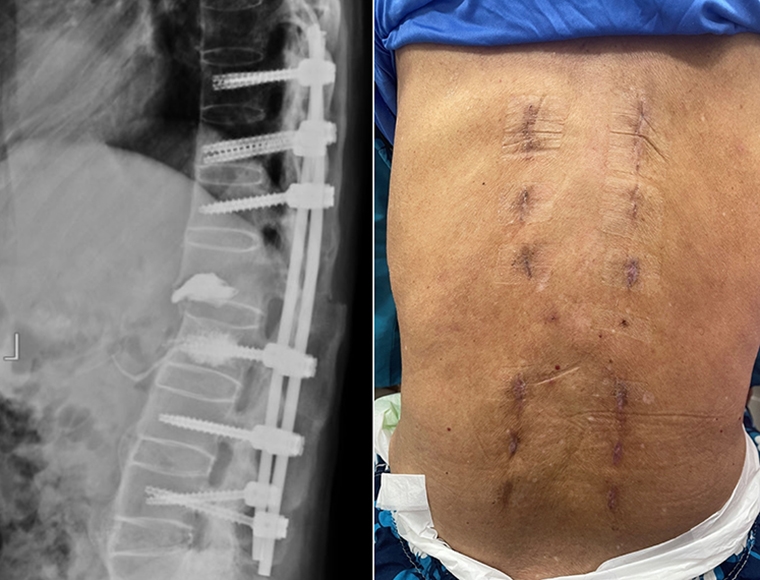

幸運的是,張先生並未出現神經壓迫症狀,下肢肌肉力量與知覺皆正常。考量到脊椎不穩定的危險性,喻醫師迅速幫張先生安排從胸椎第十節到腰椎第四節的微創脊椎固定手術。

相較傳統手術,微創手術僅需在脊椎釘入口處開小傷口,最大程度保留肌肉及周邊組織。此外,手術中也搭配了電腦斷層導航系統,提高手術精準度及縮短手術時間,不僅能大幅減輕術後疼痛,也讓患者恢復速度更快。